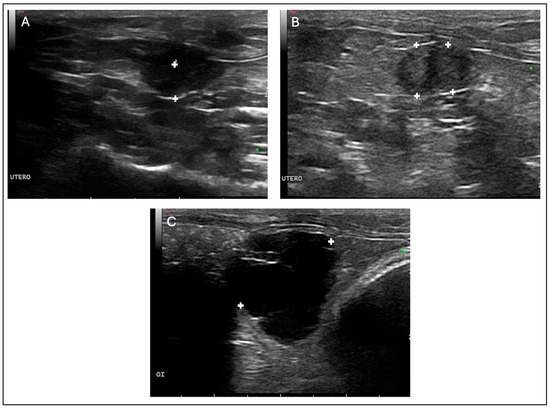

On the day following the procedure, a seroma was observed, which ruptured and ulcerated on the third postoperative day (Figure 3A). The lesion was resolved with drainage, wound cleaning three times daily with sterile saline solution, and topical application of nitrofurazone (2 mg/g, Furacin, SEID Laboratories, Barcelona, Spain). Antibiotic prophylaxis was extended to 7 days to prevent secondary infection.

Figure 3.

Timeline of postoperative follow-up of a guinea pig (Cavia porcellus) that underwent ovariohysterectomy and was diagnosed with HEC and rete ovarii cysts. Ulcerated seroma observed on day 3 (A); wound approximately 90% healed at 14 days after surgery (B); complete healing achieved by day 21, with no signs of recurrence (C).

The wound healed without further complications. At 14 days post-surgery, approximately 90% of the incision had closed (Figure 3B), and by day 21, the wound was completely healed (Figure 3C). The patient was clinically stable, with no recurrence of discomfort or pain during urination or defecation. The prescribed buprenorphine (0.01 mg/kg SC) was not required for additional analgesia.